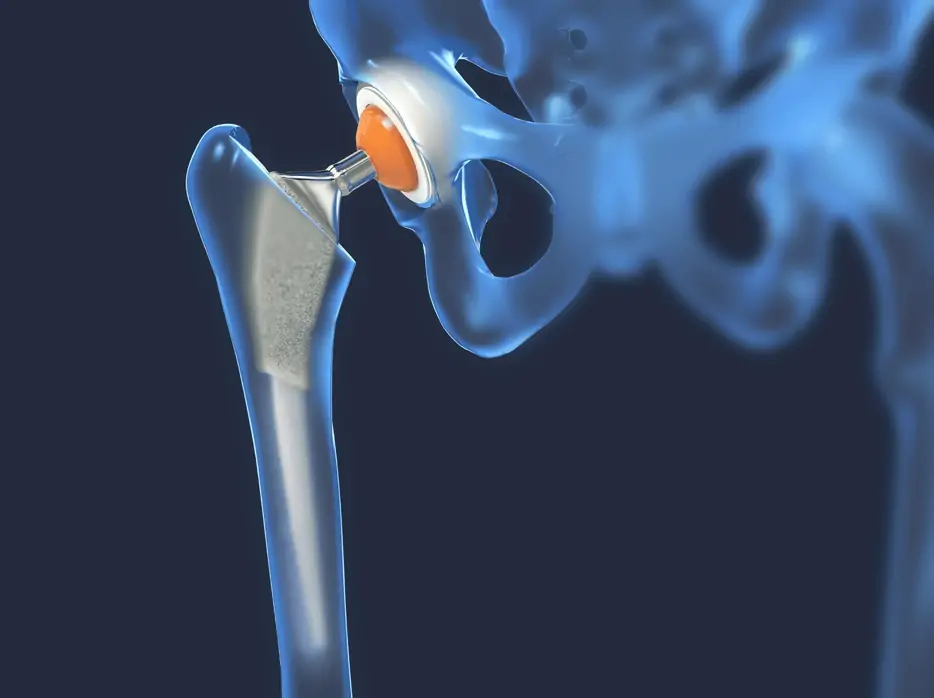

تعویض مفصل

تعویض مفصل یک روش پیشرفته جراحی برای جایگزینی مفصل آسیبدیده با یک مفصل مصنوعی با دوام بالا است. این روش برای بیماران مبتلا به آسیبهای شدید مفصلی یا آرتروز پیشرفته کاربرد دارد و باعث کاهش درد و بازگرداندن عملکرد طبیعی مفصل میشود.

در کلینیک فیزیوتراپی خانه سلامت، تعویض مفصل با استفاده از تجهیزات پیشرفته و توسط جراحان متخصص انجام میشود. این رویکرد تضمین میکند که بیمار بهترین نتیجه درمانی را با کمترین درد و دوران نقاهت ممکن تجربه کند.